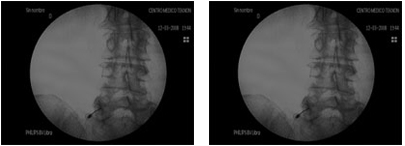

Therapeutic blocks interrupt nerve impulses and the concomitant sympathetic and motor reflexes, causing temporary analgesia, reflex interruption, and pain relief for a longer period than the local anaesthetic itself. All of this means that repeated nerve blocks constitute a treatment for chronic pain. They are performed under fluoroscopy, using electrostimulation and contrast medium to verify the exact nerve to be blocked.

A lumbar sympathetic nerve block is a procedure used to diagnose, reduce or eliminate pain caused by autonomic nerves that are affected by trauma, surgery or vascular disease.

The key to this treatment is to inject at the specific point using a proven technique, which requires the use of fluoroscopy.

Epiduroplasty

Epiduroplasty involves inserting a special catheter into the spine, under fluoroscopic guidance and in real time, in order to separate the fibrotic tissue surrounding the nerves, allowing us to inject an anti-inflammatory drug through it.